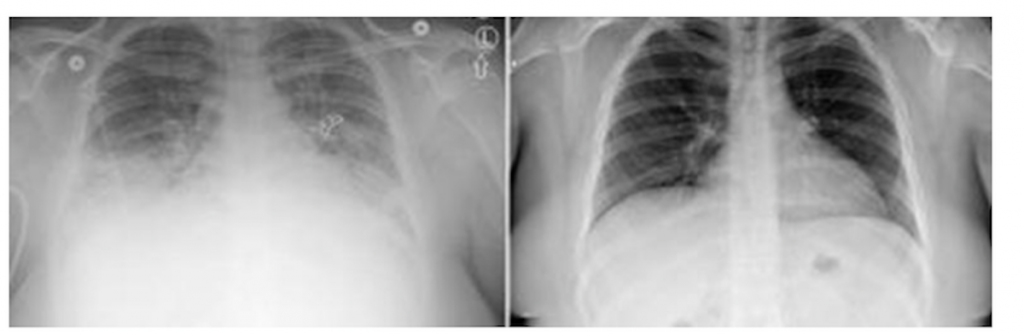

The new study examined the 2019 outbreak of vaping lung injuries, which sickened thousands of people across the country and killed at least 68. Analyzing state-level data, researchers found that states where marijuana was legal for adults had a 42% lower incidence of cases.

The lone exception among legal-cannabis states was my home state of Massachusetts, where the incidence of the disease (known as EVALI, or VAPI) was in the top fifth of all U.S. states. Other legal states were in the bottom half.

Not a single VAPI case was traced to a regulated cannabis product in Massachusetts.

To the best of my knowledge, despite Massachusetts’s unusually high incidence of vaping-related lung injuries, not a single case has been traced to a product sold on our regulated cannabis market.